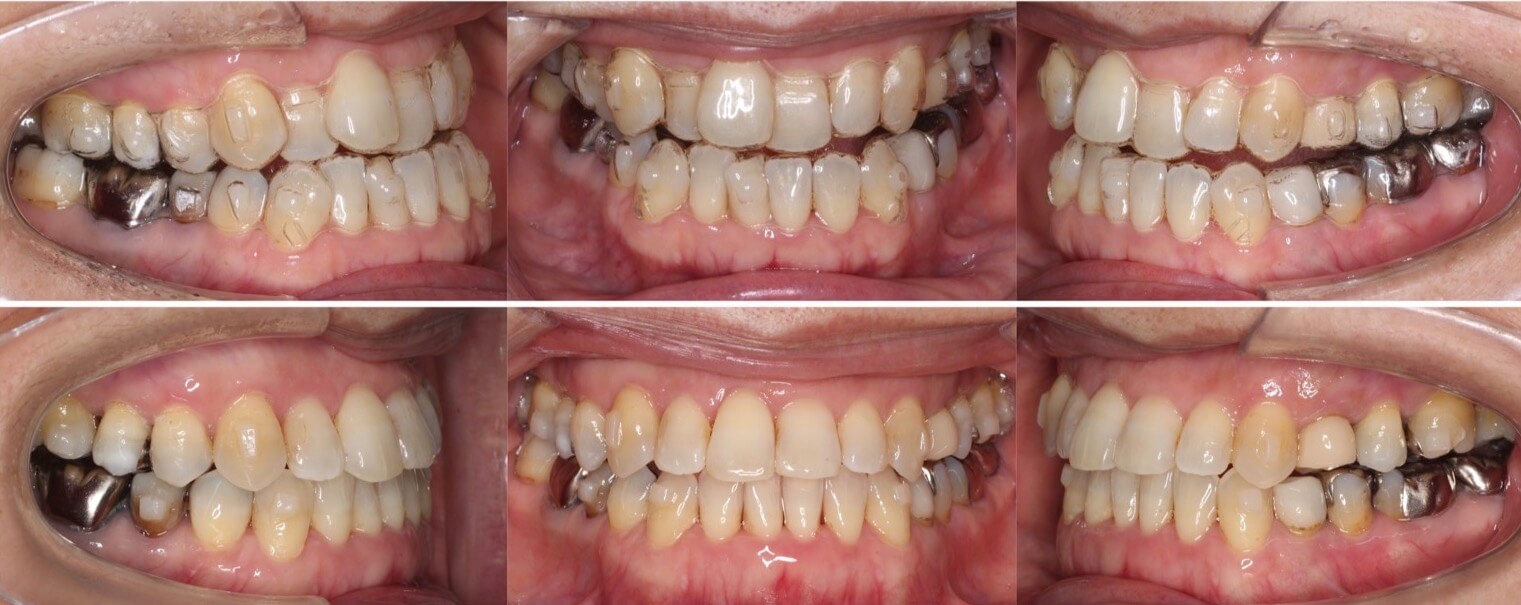

46歳女性・唇側矯正装置・抜歯

<症例概要>

主訴:前歯と口元の突出

年齢・性別:43歳女性

住まい:千葉県佐倉市

症状:叢生・上下顎前歯唇側傾斜

治療方針:上左右5番・下左右4番(計4本)

治療装置:唇側矯正装置

固定装置:ナンスホールディングアーチ

治療期間:3年

リテーナー:下フィックス+上下クリアタイプ

治療費用:968,000(税込)

代表的副作用:痛み・治療後の後戻り・歯根吸収・歯髄壊死・歯肉退縮

▶︎その他の副作用

前歯の突出のため口が閉じづらいことを気にされていて矯正治療を希望された患者さんです。年齢的に抜歯を行うか迷ったのですが、患者さんの主訴を優先して抜歯矯正により前歯を後方移動させました。抜歯部位については、上の歯並びは治療歯である第二小臼歯(5番)を選択しています。その分、治療期間は3年を超えてしまったのですが、理想的な横顔になりました。

43歳女性・唇側矯正装置・抜歯

ミドルエイジの矯正治療で抜歯方針を選択する場合は、細心の注意を払います。これは、前歯が後方に引き下がりすぎる可能性があるからです。事前に横顔のシミュレーションを確認していただき、ほうれい線が深くなるなどのリスクも承諾の上、治療を開始しました。治療後はバランスの良い横顔になりました。

主訴:口元の突出

住まい:千葉県八千代市

症状:上下顎前歯唇側傾斜・正中離開

治療方針:上下左右4番(計4本)

治療期間:2年9か月

リテーナー:上下フィックス+プレートタイプ